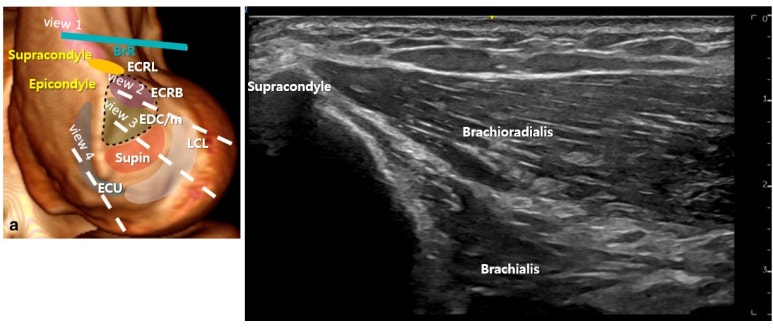

가장 흔한 질환이 테니스 엘보,** 공통 신전근 힘줄의 문제죠. 공통 신전근 힘줄은 모두 상완골 외상과에 부착되어 팔꿈치 바깥쪽 통증이 나타납니다. ## · 공통 신전근 힘줄(CET, Common extensor tendon) 손목과 손가락을 신전하는 4개의 근육들이 형성하는 공통 힘줄 · 단요측수근신근(ECRB) · 총수지신근(EDC) · 소지신근(EDm) · 척측수근신근(ECU) 팔꿈치 바깥쪽 곡지혈 주변 해부 논문들을 중심으로 살펴볼건데요. 왼쪽 카데바의 상완요골근(BrR)부터 시작해서 공통 신전근 건(CET)의 척측수근신근(ECU)까지 쭉 스캔해 내려갈 겁니다. 오른쪽 그림의 부착부를 중심으로 스캔 단면을 나눠서 보겠습니다.

첫번째는 상완골 상과(supracondyle)에 프로브를 가로로 댄 영상입니다. 프로브 위치를 민트색으로 표시했는데, 곡지혈 위쪽에 있는 주료혈 부위입니다. 상완골 상과에 부착되는 상완요골근(Brachioradialis)과 상완근(Brachialis)이 보입니다. 두 근육 다 부착부 통증이 나타나기 때문에 팔꿈치 바깥쪽 통증에 꼭 체크해봐야 할 근육입니다. 프로브를 조금 더 아래로 이동하면 상완골 상과에 부착되는 장요측수근신근(ECRL)이 보입니다. 장요측수근신근은 외상과보다 근위부인 상과에 부착되지만 일부 섬유가 단요측수근신근건과 합쳐집니다. 외상과로 장력이 전달되어 팔꿈치 바깥쪽 통증이 나타날 수 있으므로 외상과염 환자가 왔을 때 단요측수근신근과 함께 체크해봐야 합니다.